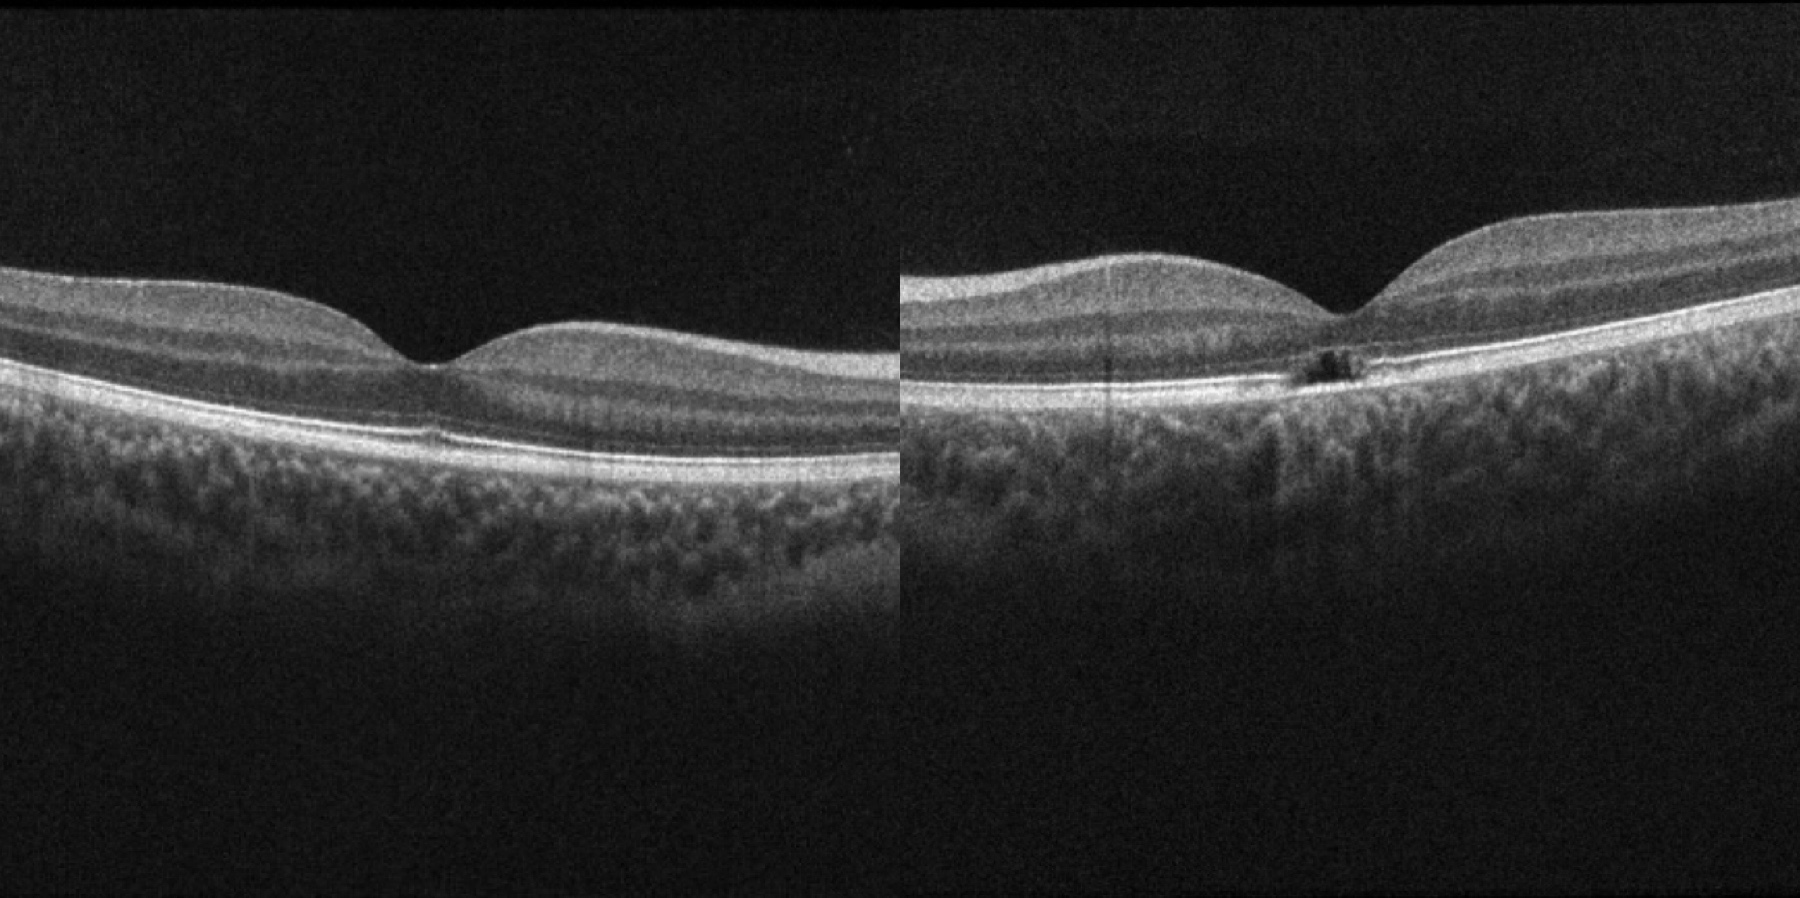

眼底照片:正常眼底(左)、黄斑部黄白色病灶(右)

彭鸿钧教授安慰孩子家长不要焦虑,表示医院会给孩子做全面检查。随后,他先给小董做了散瞳验光和眼底检查。散瞳验光检查发现,小董右眼矫正视力能达到正常1.0,左眼矫正视力只有0.5。而眼底检查发现,左眼的黄斑区有一片黄白色的病灶。